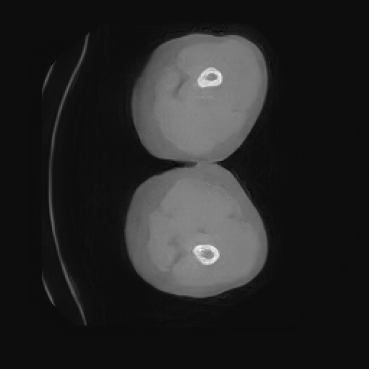

As shown in Figure 5, the generated slices exhibit high consistency across adjacent slices. The anatomical structures and semantic patterns are smoothly and coherently preserved between slices, indicating that our model is capable of generating 3D-consistent synthetic images rather than isolated 2D slices.

In contrast, the segmentation result of synthetic data generated by SegGuidedDiff using 2D semantic map slices shows significantly lower performance (Dice = 0.602). Notably, SegGuidedDiff generates images slice-by-slice in 2D without modeling the full 3D spatial context. As a result, the synthesized volumes often suffer from inter-slice inconsistencies and unrealistic spatial structures, which negatively impact the downstream segmentation performance.

Our Med-LSDM-generated data, in contrast, achieves a Dice score of 0.70964, which is much higher than SegGuidedDiff and closely approaches the real data test performance. This indicates that our method’s 3D generation strategy successfully captures anatomical coherence across slices and produces realistic volumetric data. It is also important to note that the synthetic volumes are directly saved in NIfTI format without any post-processing, demonstrating the practical applicability and robustness of our framework.

The hypothesis of this experiment is that if the synthetic images generated by our model resemble real medical images in distribution, a segmentation network trained on real data should yield similar performance on synthetic data. By comparing the segmentation results across real and synthetic images, we can quantitatively assess the structural fidelity and semantic consistency of the generated data. The results confirm that segmentation performance on synthetic images is highly comparable to that on real images, indicating that our model successfully captures anatomically relevant structures. This suggests that synthetic data are not only realistic but also potentially beneficial as an augmentation strategy to improve segmentation tasks. Visualizations of the segmentation output are presented in Figure 6.